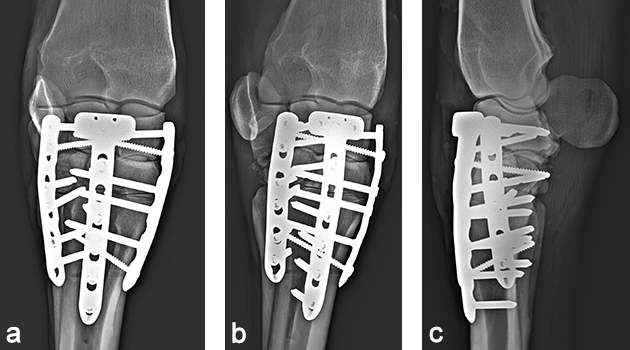

The day after admission, the mare was placed under general anesthesia in dorsal recumbency for a partial carpal arthrodesis of the right carpometacarpal and middle carpal joints. The middle carpal joint was examined arthroscopically, and all visible articular cartilage was removed by using a combination of manual (bone curette) and motorized (shaver/burr) instrumentation (Fig 6). A 4.5 mm drill bit was used to drill across the carpometacarpal joint surfaces. A cancellous bone graft harvested from the sternum was loosely packed into the repair through an arthroscopic portal with the leg in flexion. Following graft insertion, implants were placed using a minimally invasive technique, tunneling the plate under the skin and joint capsule, and stab incisions for screw insertions. A 6-hole LCP Equine T-plate 4.5 was applied to the dorsal aspect of the limb deep to the extensor tendons and joint capsule through an enlarged arthroscopic portal between the extensor carpi radialis and common digital extensor tendon using a plate passer. A 4.5 mm cortex screw was placed in the first hole of the shaft of the plate to compress the plate to the bone. Two 5.0 mm locking screws were placed in the holes of the horizontal portion of the plate to engage the intermediate carpal bone. A third 5.0 mm locking screw was placed into the radial carpal bone using the last hole of the horizontal portion of the plate (Fig 7). All remaining holes were filled with 5.0 mm locking screws except the second hole, which was left empty because the hole was directly over the carpometacarpal joint. A 6-hole narrow LCP 4.5 was applied dorsolaterally and a 6-hole narrow LCP 4.5 was placed dorsomedially in a similar manner. The skin incisions were closed in routine fashion, and a sterile dressing and full limb cast were applied. The mare recovered uneventfully from anesthesia with head and tail assistance.